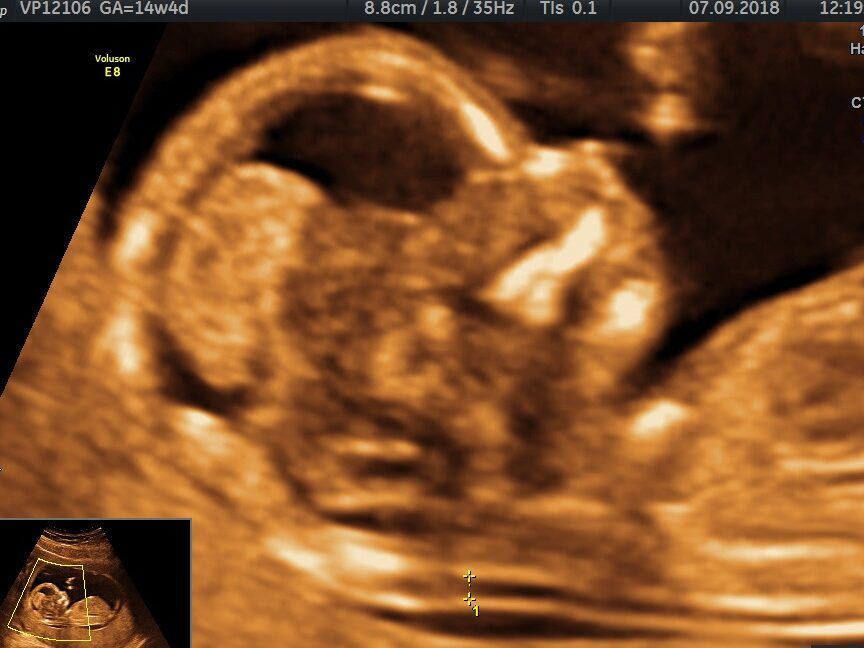

Una herramienta fundamental en el diagnóstico y seguimiento del síndrome de Down son las ecografías. Estas son un tipo de prueba médica que utiliza ondas de sonido para producir imágenes del interior del cuerpo.

Las ecografías permiten evaluar el desarrollo del feto y detectar posibles anomalías. Estas pruebas son seguras, no invasivas y se pueden realizar en diferentes etapas del embarazo. Estudios científicos han respaldado la eficacia de las ecografías en el diagnóstico del síndrome de Down.

La ecografía abdominal se realiza en el segundo y tercer trimestre del embarazo. Se aplica un gel en el abdomen de la madre y se utiliza un transductor para capturar imágenes del feto. Esta técnica permite evaluar el crecimiento y desarrollo del bebé, y detectar posibles anomalías.

• Se podrán visualizar diferentes estructuras y órganos del bebé, y se podrán obtener imágenes de alta calidad.

Una vez realizada la ecografía, los médicos analizarán las imágenes para identificar posibles características del síndrome de Down. Algunos de los marcadores que pueden indicar la presencia de esta condición incluyen el aumento del tamaño del pliegue nucal y la presencia de otros marcadores específicos.